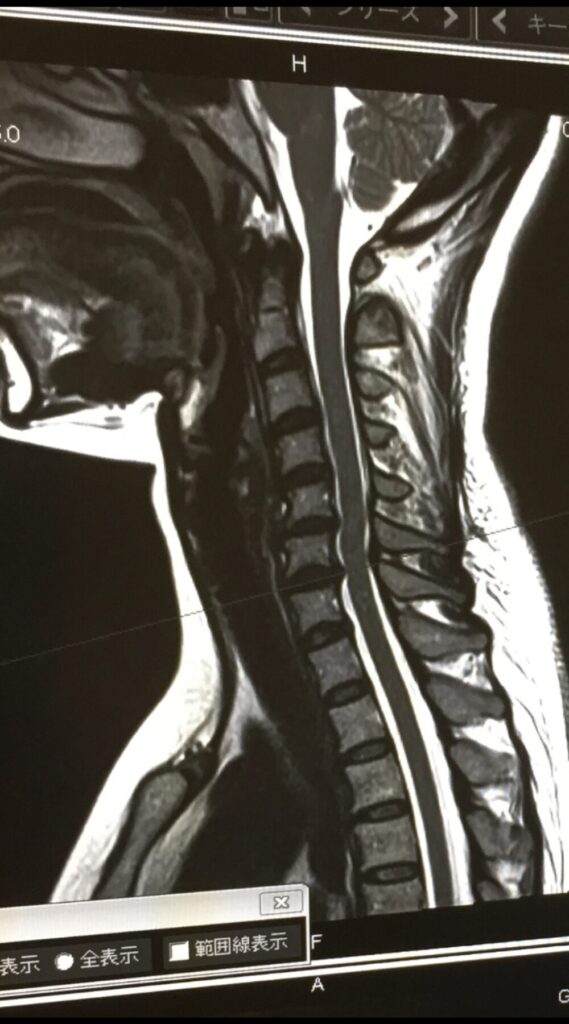

1.2 椎間板ヘルニアが首で発生するメカニズム

椎間板は、中心にゼリー状の「髄核(ずいかく)」があり、その周囲を丈夫な「線維輪(せんいりん)」という軟骨組織が何層にも重なって取り囲んでいます。この構造が、背骨にかかる衝撃を吸収し、柔軟な動きを可能にしています。

しかし、加齢による変化や、繰り返しの負担、急な外力などが加わることで、この線維輪が徐々に劣化したり、損傷したりすることがあります。線維輪に亀裂が入ると、内部の髄核がその亀裂から外へと飛び出してしまいます。この髄核の突出が「ヘルニア」と呼ばれる状態です。

首の椎間板ヘルニアの場合、飛び出した髄核が、頸椎の近くを通る「神経根」や「脊髄(せきずい)」を圧迫することで、前述のような痛みやしびれ、筋力低下といった症状を引き起こします。首は常に頭の重さを支え、様々な方向に動くため、椎間板に大きな負担がかかりやすい部位です。特に、前かがみの姿勢や不自然な姿勢が長時間続くことで、特定の椎間板に過度な圧力が集中し、ヘルニアのリスクが高まると考えられています。

神経根が圧迫されると、その神経が支配している領域(腕や手など)に症状が現れることが多く、これを神経根症と呼びます。一方、脊髄そのものが圧迫されると、手足のしびれや運動障害、歩行困難など、より広範囲で重篤な症状が出ることがあり、これを脊髄症と呼びます。首の椎間板ヘルニアでは、どちらのタイプの圧迫も起こり得ます。